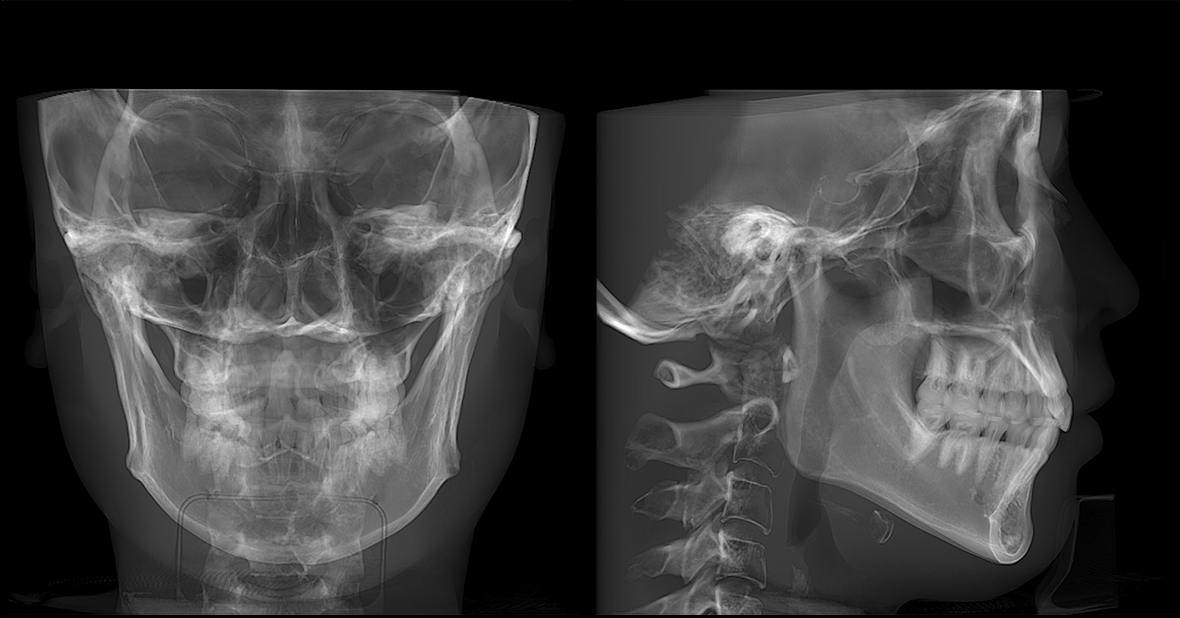

• lamtau AI頭影測(cè)量

AI頭影測(cè)量

單側(cè)頭影測(cè)量 專利 首創(chuàng)

偏頜患者的側(cè)位片左右側(cè)的影像不對(duì)稱,實(shí)際正畸測(cè)量時(shí)會(huì)產(chǎn)生較大的誤差。有方醫(yī)療推出單側(cè)頭影測(cè)量功能。這一功能有效解決了這一臨床問題,在口腔正畸領(lǐng)域廣受好評(píng),并于2023年成功獲得國家發(fā)明專利授權(quán)。

單側(cè)頭影測(cè)量